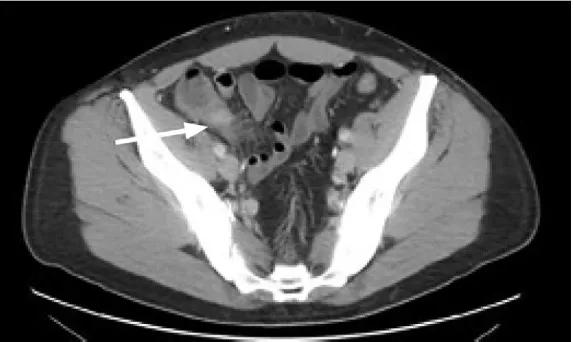

门静脉的感染从何而来?罪魁祸首就是这条已经穿孔的阑尾(图3)!

图3.坏疽穿孔性阑尾炎